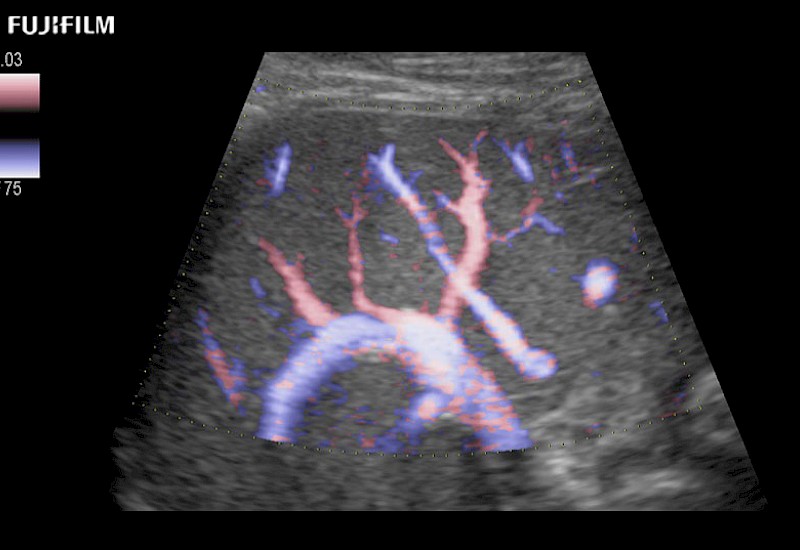

Our dedication to Surgical Oncology allows us to offer superior image quality, outstanding system reliability and intuitive use of cutting edge technology.